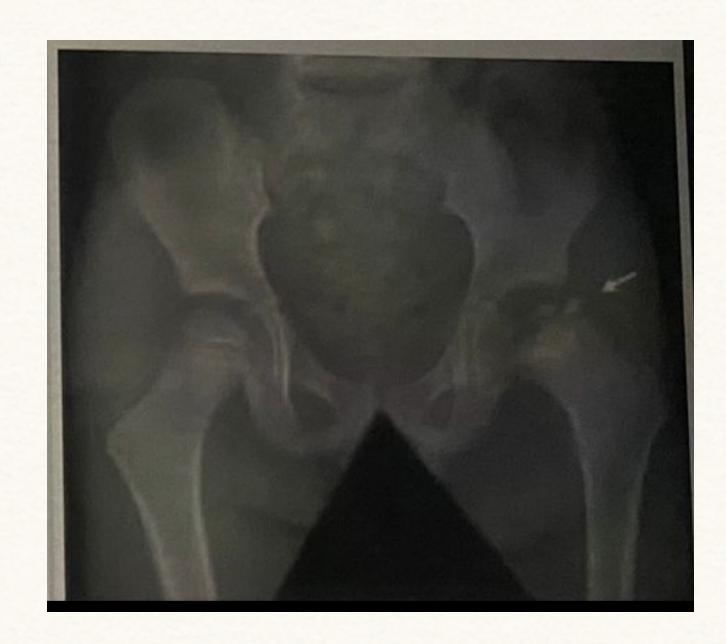

A teenager with acute onset of pain in the right hip during a run. He sustained the injury seen in the x-rays with a white arrow. This injury usually occurs due to a forceful eccentric contraction of which of the following muscles?

- C. Rectus femoris

- Sartorius

Pelvic Anatomy

Which of the following muscles is attached to the structure pointed by the arrow?

- C. Sartorius

Note: Arrow was pointing at ASIS (Anterior Superior Iliac Spine)